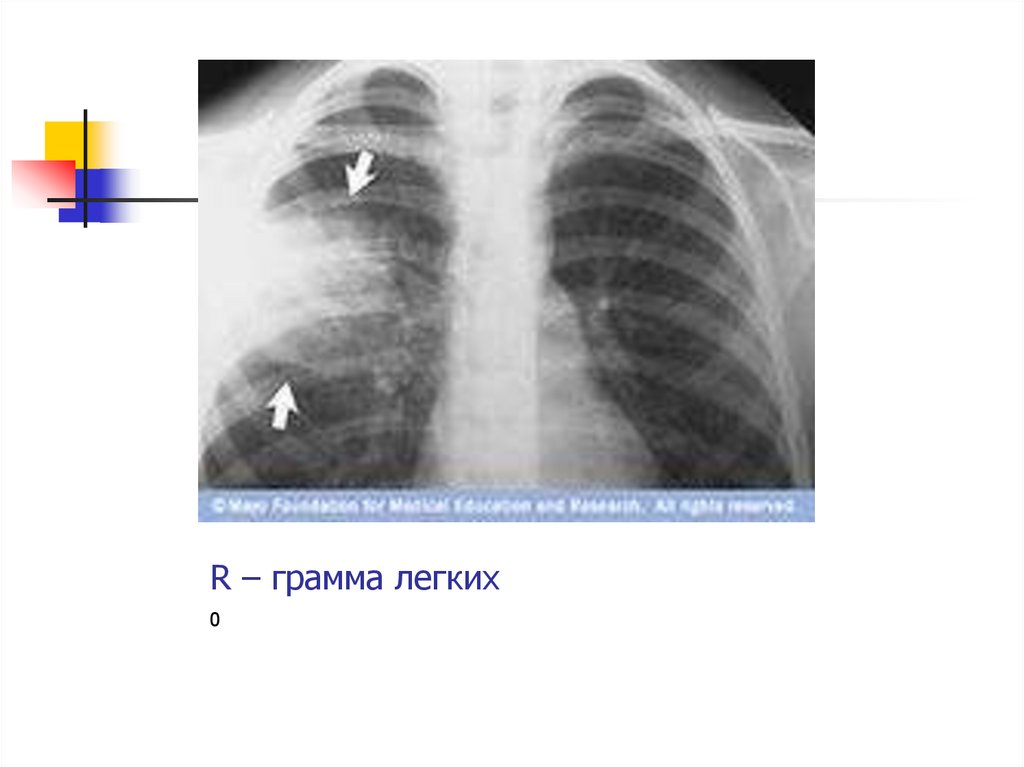

34. Инструментальные методы диагностики.

рентгенография

грудной клетки в двух

проекциях - затемнение

(инфильтрация)

поражённой доли;

- ЭКГ;

- ФВД;

- томография.

35. R – грамма легких

0